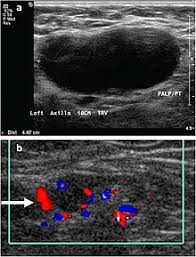

The lymph nodes in the neck are often the first place cancer cells spread to outside the primary site. If cancer is found in a lymph node, you may need a neck dissection or other additional treatment. An ultrasound does not have the resolution to see cancer cells. Ultrasounds have many limitations an ultrasound is not good enough for many aspects of cancer. Fna might also be used in patients whose cancer has been treated by surgery and/or radiation therapy , to help find out if a neck mass in the treated area is scar tissue or if it's a return (recurrence) of the cancer. Ultrasound uses sound waves to create images of the body on a computer monitor. In some cases, your ultrasound may show images of nodules that may or may not be cancerous or contain microcalcifications, which is often associated with cancer. Ultrasound imaging is a noninvasive medical test that helps physicians diagnose and treat medical conditions. Additionally, how do they test for thyroid cancer? Lymph nodes are part of the lymphatic system, which helps to protect us from infection and disease. Ultrasound guidance is used to perform thyroid biopsies and improves the diagnostic accuracy of fine needle biopsy. Carotid ultrasound tests for blocked or narrowed carotid arteries, which can increase the. But according to one study, cancer.

Colon Cancer Ultrasound Radiology Case Radiopaedia Org from prod-images-static.radiopaedia.org To see whether the cancer has spread, some or all of the lymph nodes are removed and checked for cancerous cells. We prospectively studied 19 patients referred to the institut gustave. It can be used with a fine needle aspiration test or core biopsy test to accurately direct the tip of the needle into the lump. If this lump is of concern then a biopsy would be the next step. They deliver blood from your heart to your brain. Head and neck cancers include cancers in: However, an ultrasound can tell if a lymph node has an abnormal architecture possibly because it is infiltrated by tumor. Sonography, when performed by an experienced examiner, can be used for evaluation of many pathologies in the head and neck area.

While it can't diagnose cancer, it can detect the abnormal tissues that may possibly be cancerous. Ultrasound is often one of the first line tests in the detection of cancer. For neck or thyroid mass see ent. Lymph nodes are part of the lymphatic system, which helps to protect us from infection and disease. Some of the indications for thyroid or neck ultrasound are thyroid nodules, goiter, thyroid cancer and other neck masses. Ultrasound imaging is a noninvasive medical test that helps physicians diagnose and treat medical conditions. Part of the throat (cancers of the oropharynx and tonsils, nasopharynx and hypopharynx) the nose or sinuses (nasal and sinus cancer) the salivary glands. Ultrasound guidance is used to perform thyroid biopsies and improves the diagnostic accuracy of fine needle biopsy. Sonography has an accuracy rate of about … Fna might also be used in patients whose cancer has been treated by surgery and/or radiation therapy , to help find out if a neck mass in the treated area is scar tissue or if it's a return (recurrence) of the cancer. If the person has a lump in the neck, an fna can show if the mass is from cancer spread. It can be used with a fine needle aspiration test or core biopsy test to accurately direct the tip of the needle into the lump. It can detect abnormal tissues, growths, and cysts and give a suspicion of cancer based on how those images look.